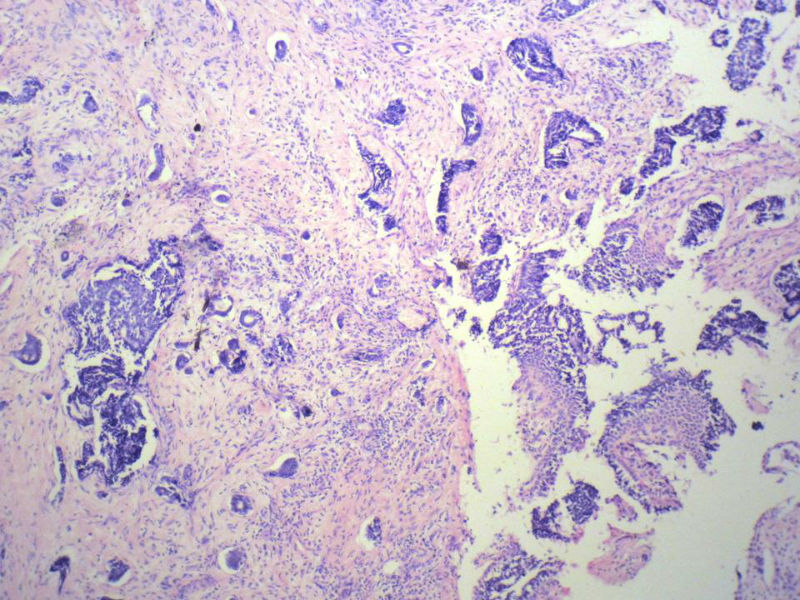

男,76岁,鼻塞两个月,CT提示左上颌窦占位,局部骨质破坏,口腔硬腭下降,局部活检。

左上颌窦占位图1

名称:图1

描述:幻灯片2

腺样囊性癌

腺样囊性癌,图像很典型的